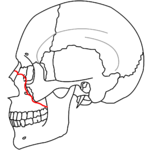

| Le Fort III fractures | |

At the beginning of the 20th century, René Le Fort mapped typical locations for facial fractures; these are now known as Le Fort I, II, and III fractures (right).[6] Le Fort I fractures, also called Guérin or horizontal maxillary fractures,[13] involve the maxilla, separating it from the palate.[14] Le Fort II fractures, also called pyramidal fractures of the maxilla,[15] cross the nasal bones and the orbital rim.[14] Le Fort III fractures, also called craniofacial disjunction and transverse facial fractures,[16] cross the front of the maxilla and involve the lacrimal bone, the lamina papyracea, and the orbital floor, and often involve the ethmoid bone.[14] are the most serious.[17] Le Fort fractures, which account for 10–20% of facial fractures, are often associated with other serious injuries.[14] Le Fort made his classifications based on work with cadaver skulls, and the classification system has been criticized as imprecise and simplistic since most midface fractures involve a combination of Le Fort fractures.[14] Although most facial fractures do not follow the patterns described by Le Fort precisely, the system is still used to categorize injuries.[5]